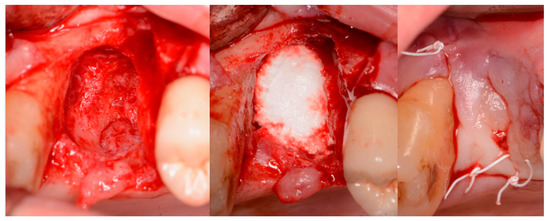

A critical question is about what happens histologically to the graft and at what stage during healing. For example, when delayed socket grafting was performed at a site where a large defect was present following extraction (Figure 18, left), a healing period of 3 weeks post-extraction was needed, allowing primary closure post-graft. This gives us more predictability and simpler surgery, plus two attempts to clean the site. EthOss graft material was placed into the socket (Figure 18, middle) and primary closure with the flap was achieved and secured with sutures (Figure 18, right). Intraoral physical exam and radiographic measurement showed all sites to have regenerated vertically 3–6 mm and horizontally 4–6 mm with new host bone allowing for successful placement of the implants. A core sample was obtained from one case to confirm the series to be in line with earlier findings. Histology was performed by core biopsy at 10 weeks following graft placement and demonstrated well-preserved reactive (woven) trabecular bone with intertrabecular tissue composed of uniformly collagen-rich myofibroblastic tissue and 60% of the core consisting of bone (Figure 19).

Figure 18.

Delayed socket grafting with flap exposure of the site (left), placement of EthOss graft to fill the defect (middle) and flap placement to achieve primary closure (right).

Figure 19.

Histology of the core sample obtained following 10 weeks of graft site healing demonstrating well preserved reactive (woven) trabecular bone with intertrabecular tissue composed of uniformly collagen-rich myofibroblastic tissue and 60% of the core consisting of bone.